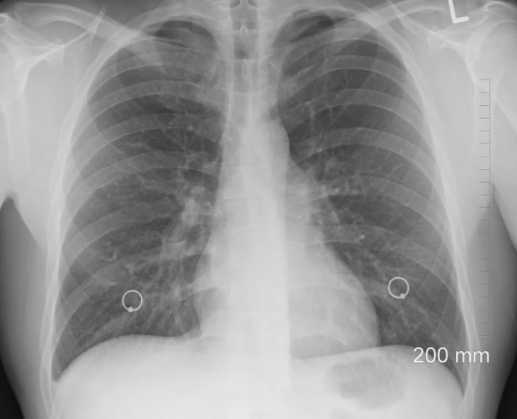

4. 폐암과 폐색전증

폐암의 경우는 드물기는 하지만 발생하면 갈비뼈 쪽에 통증이 발생한다. 요즘 우리나라에서 폐암환자가 급증하고 있다는 통계가 있으며, 갈비뼈 근처에 통증과 더불어 기침, 가래, 호흡곤란, 구토, 어지러움 등의 증상등이 나타날 수 있다.

또한 폐색전증일 가능성도 있는데 이는 기침과 어지러운 증상 그리고 호흡곤란과 더불어서 심장이 두근거리는 증상이 나타날 수 있다.